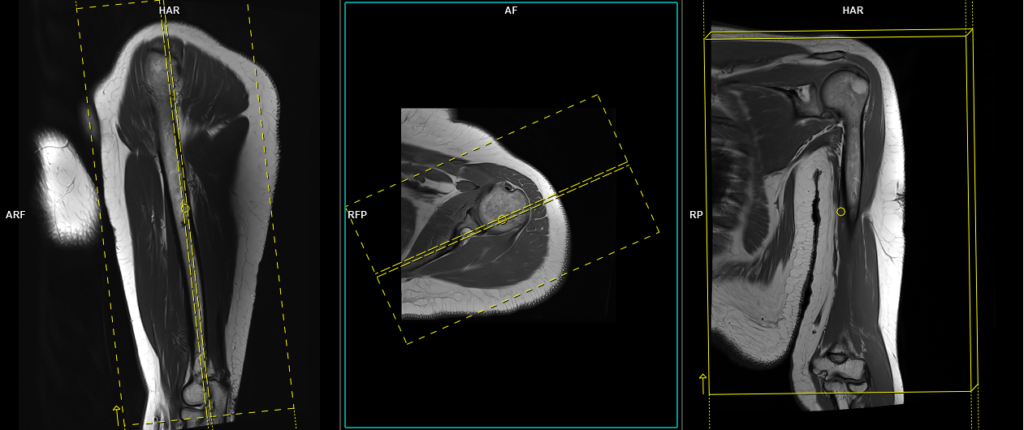

T1 tse coronal 3mm

Plan the coronal slices on the axial plane and angle the planning block parallel to the scapular blade. Check the planning block in the other two planes. An appropriate angle must be used in the sagittal plane (parallel to the humerus). Slices must be sufficient to cover the whole upper arm from anterior to posterior. The field of view (FOV) must be big enough to cover both the shoulder and elbow joints. Adding saturation bands over the chest will reduce breathing and arterial pulsation artifacts. For the phase direction, you can choose either right to left or head to feet, and a minimum 100% oversampling is recommended to avoid wrap-around artifacts.

Parameters

TR 400-600 | TE 15-25 | SLICE 5 MM | FLIP 150 | PHASE R>L | MATRIX 448X384 | FOV 350-400 | GAP 10% | NEX(AVRAGE) 2 |

T2 stir coronal 3mm

TR 3000-4000 | TE 110 | FLIP 150 | NEX 2 | SLICE 5 MM | MATRIX 384X320 | FOV 350-400 | PHASE R>L | GAP 10% | TI 150 |